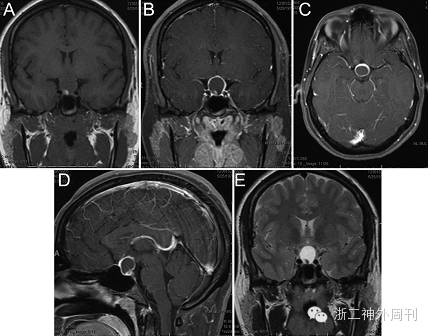

还有一位8岁男孩,因性早熟和发现鞍上区肿物就诊,后证实肿物为GCT[4];更有意思的是,Losa报道一例肢端肥大症的42岁女性,术后病理证实肿瘤为GCT(图6),作者甚至认为GCT可能分泌GH,导致患者出现相关内分泌症状[5];Mumert等还报道过一例似Rathke囊肿的囊性GCT[6](图7)。本例病人为老年男性患者,平素体健,在偶然的一次体检中发现此鞍上病变,根据病史及影像学表现,我们一开始亦考虑诊断为脑膜瘤和颅咽管瘤,后经术中所见和术后病理分析,确诊为GCT。因此,对于术前临床症状不明显、病变位于鞍上/垂体柄部位、术中肿瘤质地较坚韧的鞍区病变患者,需怀疑GCT可能。

图7. Mumert等报道一例囊性GCT,肿物呈环形均匀强化,囊内可见一小结节[6]。